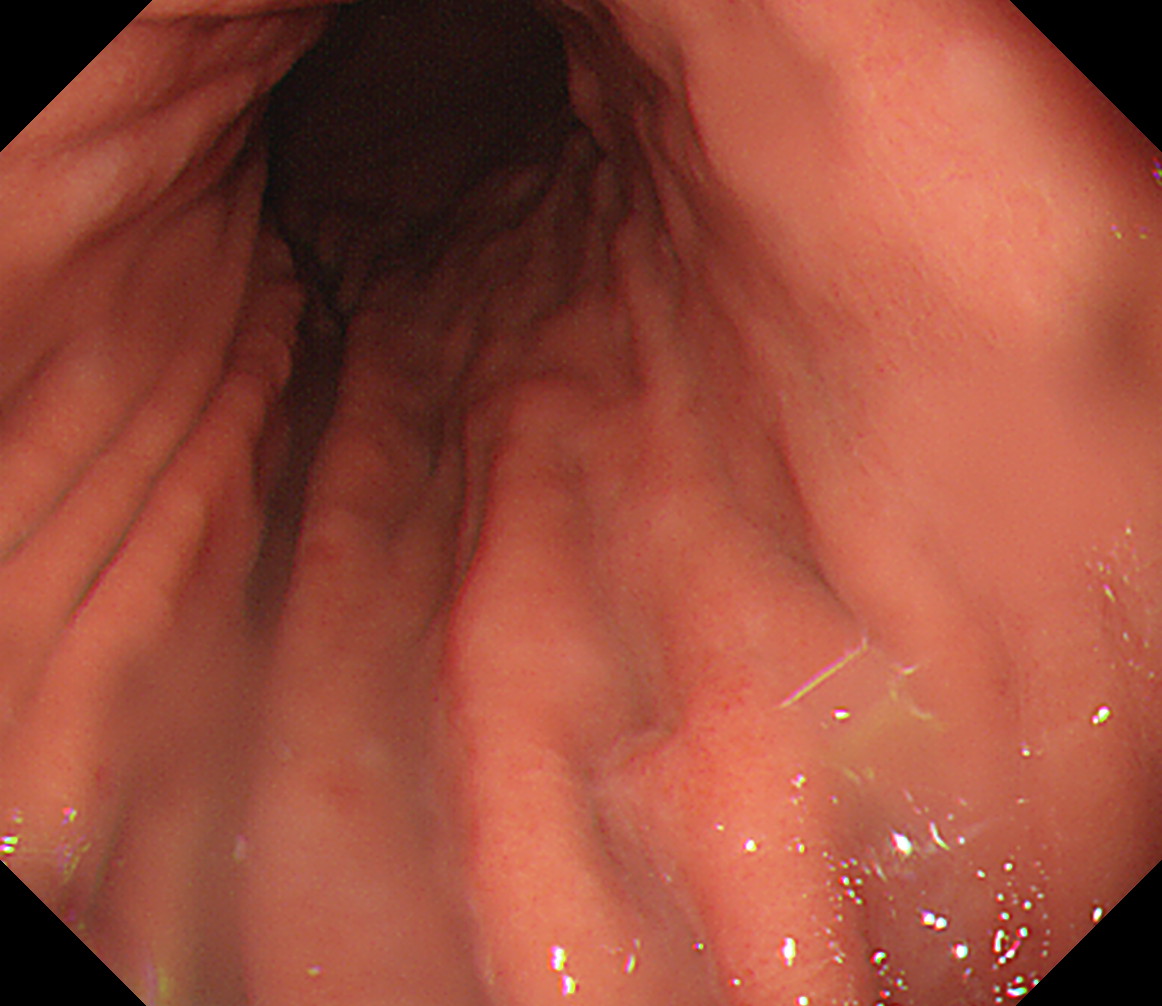

28 体中部後壁 いったんカメラを噴門まで引き上げて胃体中部を決定し

後壁から反時計回り

胃角部大弯

29 体中部小弯 体下部後壁

30 体中部前壁 体下部小弯

31 体中部大弯 体下部前壁

32 体上部後壁(分水嶺) 分水嶺は胃体上部と穹窿部の境界だが病変の多い部分なのでこの画面に分水嶺全体を入れる